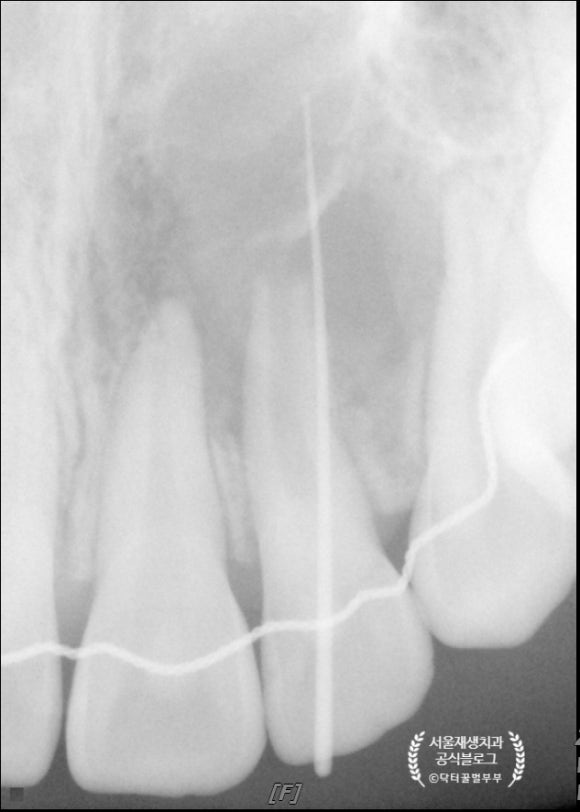

둘째 날입니다.

통상 첫 번째 방문과1주일 간격을 두고 재내원합니다.

재생근관치료는 두 번의 내원으로 진료가 끝납니다.

3회 이상 내원하면서

뿌리 끝이 닫히는지 확인해야 하는 근단형성술에 비하면 엄청난 발전이지요^^

이 날은 상방에 근관 내에 MTA를 도포합니다.

MTA는 치과치료용 시멘트라고 이해하시면 편합니다.

근데 이제

세포분화와 재생, 성장을 촉진하는....^^

재생근관치료(=신경재생술)과 찰떡궁합이지요.

MTA를 빼놓고는 재생근관치료가 성립되지 않는답니다.